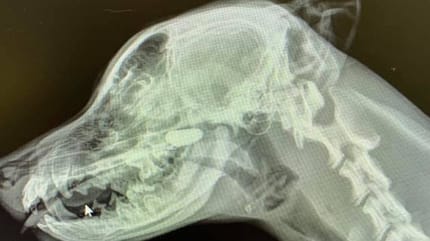

Para poder dar con el cuerpo extraño, la veterinaria se dispuso a realizarle unas radiografías al perro.

La primera imagen del pecho no reveló nada sospechoso, por lo que se tomó otra radiografía de la zona lateral de la cabeza y el cuello.

En la nasofaringe, se podía observar claramente una piedra que se había introducido en las fosas nasales del can